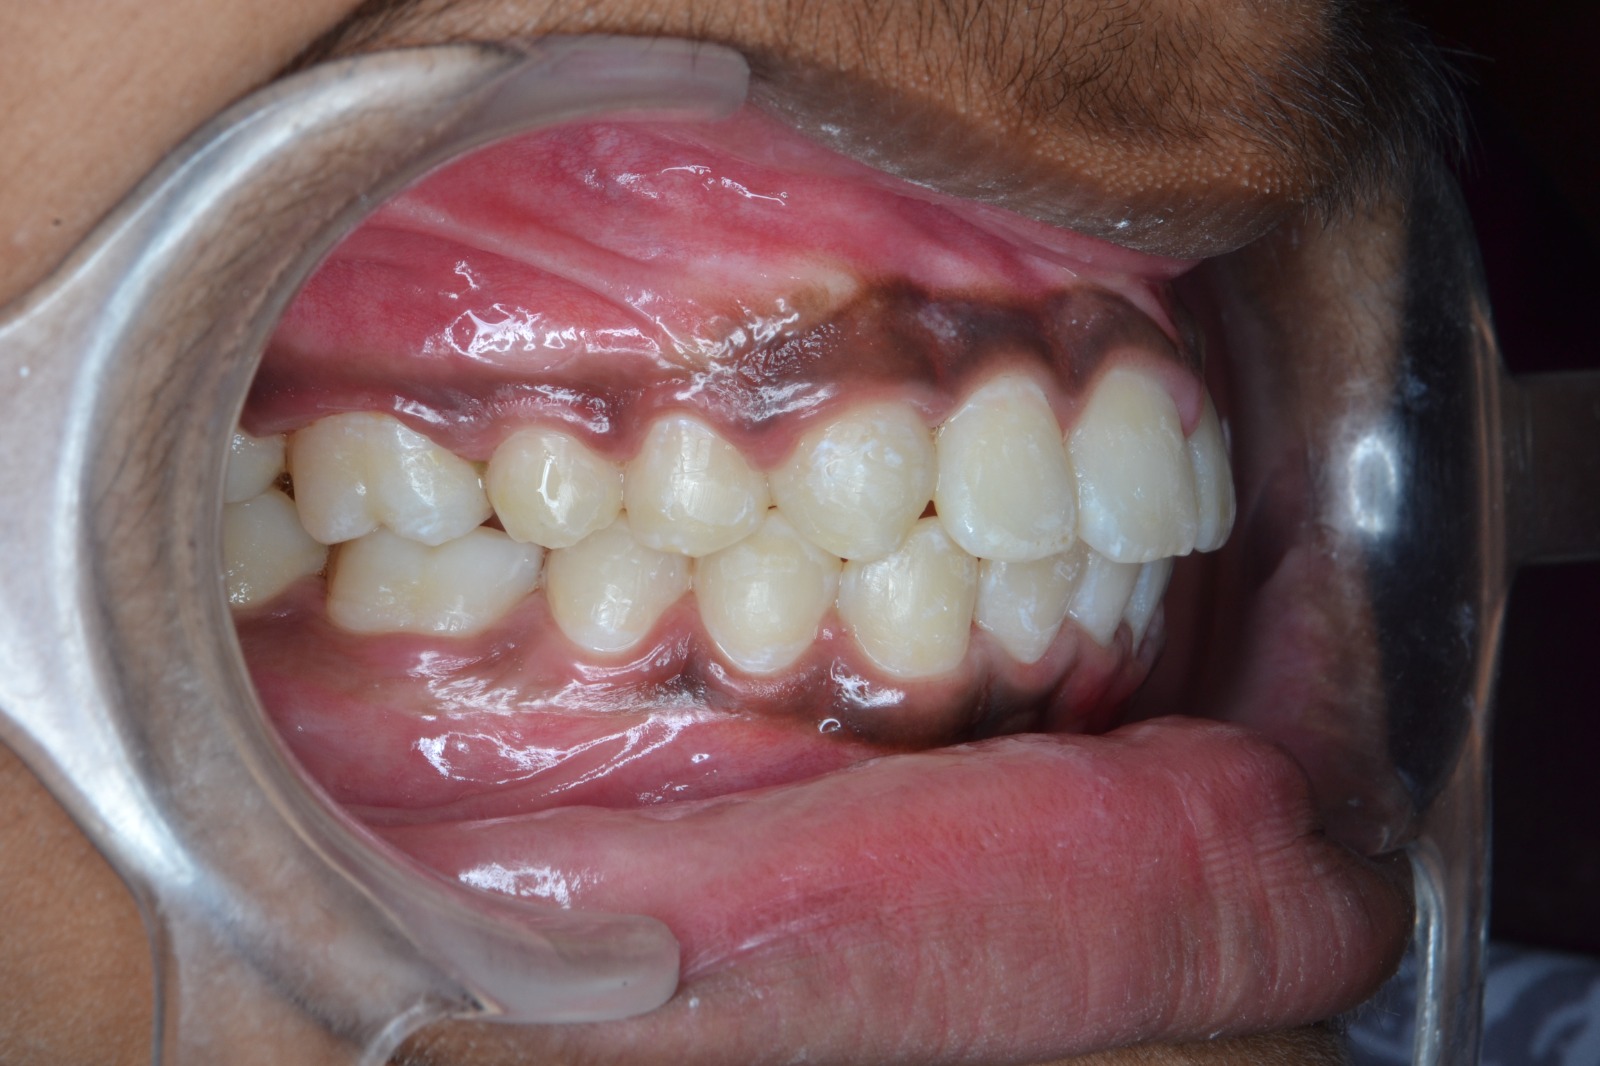

After/Before

See stunning smile transformation before and after

Before After